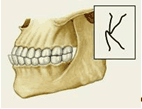

Различают несколько вариантов нормального П. (ортогнатический, прогенический, прямой, бипрогнатический). Они характеризуются смыканием зубных рядов на всем протяжении и отличаются друг от друга лишь особенностями смыкания функционально ориентированных групп зубов, в частности передних. Эталонным принято считать ортогнатический прикус (рис. 5, а), при котором верхний зубной ряд на всем протяжении перекрывает нижний, а во фронтальном участке верхние резцы перекрывают нижние не более чем на 1

/3

коронковой части зуба; между резцами верхней и нижней челюстей имеется режуще-бугорковый контакт. Прогенический прикус (рис. 5, б) отличается умеренным выстоянием нижнего зубного ряда. Прямой прикус (рис. 5, в) характеризуется тем, что верхние резцы не перекрывают нижние, а смыкаются режущими краями. При бипрогнатическом прикусе (рис. 5, г) верхние и нижние резцы наклонены в сторону преддверия рта, но между ними сохранен режуще-бугорковый контакт. Для всех вариантов нормального прикуса обязательным условием является нормальное функционирование зубочелюстной системы.

Рис. 5а). Схематическое изображение челюстей при основных разновидностях нормального прикуса (вид сбоку): ортогнатический прикус.